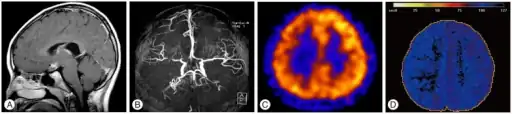

T1-weighted MR image of moyamoya disease. Flow void in the basal ganglia is indicated by the arrow. | |

Magnetic resonance angiography (MRA) is also useful in diagnosing the disease with good correlation with Suzuki's grading system.[14]

Often nuclear medicine studies such as SPECT (single photon emission computerized tomography) are used to demonstrate the decreased blood and oxygen supply to areas of the brain involved with moyamoya disease. Conventional angiography provides the conclusive diagnosis of moyamoya disease in most cases and should be performed before any surgical considerations.